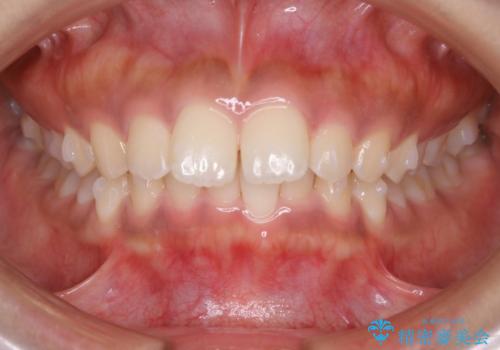

インビザライン矯正 歯を抜かずに出っ歯を改善!

- 出っ歯と前歯の隙間が空いていることを気にされて来院されました。

また、自然な感じで口元を下げていとのことでした。

奥歯のかみ合わせが問題なかったため、上顎の前歯の隙間を閉じるとともに、上顎の歯の側面を削ることをメインにして、出っ歯を改善する治療計画としました。

上顎の歯の傾きを変えるうえで、下顎の歯とのバランスのことも考え、下顎の歯の側面も削ることを加えています。

また、今回は口元を変えたい中に、劇的な変化は避けたいとのことだったので、抜歯をしない計画としています。

抜歯をしない場合、口元の変化は感じにくいですが、前歯の傾きが変わることで、口の閉じやすさは感じていただけたとのことです。

症例にもよりますが、本症例は奥歯のかみ合わせに問題がなかったので歯の側面を削ることメインに、前歯の傾きを改善することができました。

抜歯を行う場合や抜歯をしなくても奥歯の位置をずらす場合は、治療期間が長期化することが多いですが、今回は歯を削ることで改善できたため、短期間で治療を完了することができました。